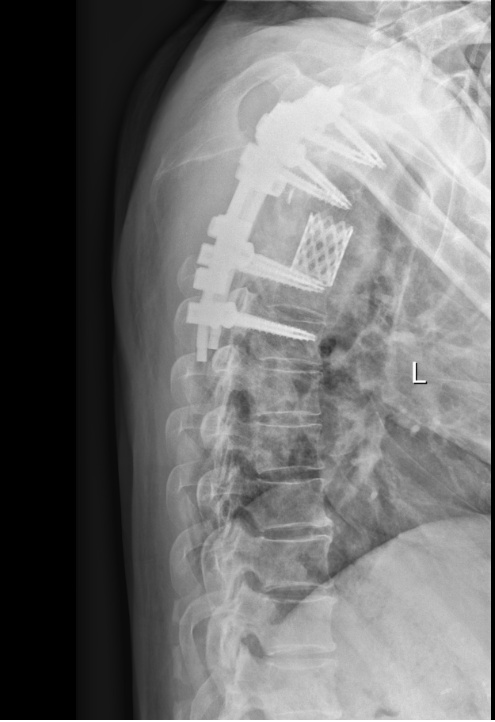

一切准备就绪,在麻醉科、手术室的全力配合下,张伟滨主任带领杨军副主任医师、刘卓超医生等组成的精锐手术团队,实施了这场高难度精细手术。团队凭借娴熟的技艺和丰富的临床经验,小心分离肿瘤组织,完整切除受侵椎体,同时完成脊柱稳定性重建。历经6小时的精雕细琢与沉稳奋战,被肿瘤包裹的硬脊髓膜恢复有力搏动,这既是手术成功的标志,也为患者神经功能的恢复带来了希望。

患者术后影像图/术后康复训练

术后第二天,许先生原本完全无法动弹的双下肢,出现了明显的肌力恢复(达到M2级)。手术成功只是第一步,术后的精细护理同样是恢复的关键。在精心治疗和专业护理下,随着术后系统性康复治疗的推进,许先生的恢复速度令人鼓舞,肌力逐步提升至M4级,还能自主坐起,重新找回了对身体的掌控感,顺利出院。“谢谢瑞金医院,谢谢医生护士们,是你们给了我第二次生命!”许先生感慨地说:“我亲身感受到了瑞金医院顶尖的医术,更体会到了医护人员全程细致贴心的救治与关怀。”